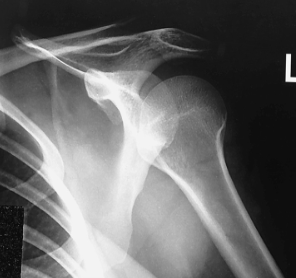

is this a normal or dislocated shoulder? in which direction is it dislocated?

dislocated, anterior